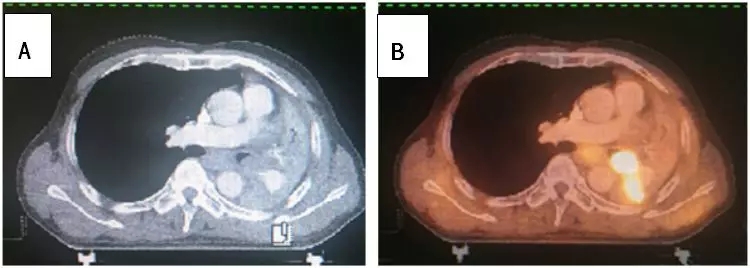

图1:患者,邹xx,男,61岁,临床诊断左肺鳞癌,经化疗2周期后病情进展。图A—增强CT示左肺下叶鳞癌伴左肺下页不张,肿瘤组织与不张肺组织边界难以界定;图B—PET/CT能够将肿瘤原发病灶和肺不张进行更好的区别。